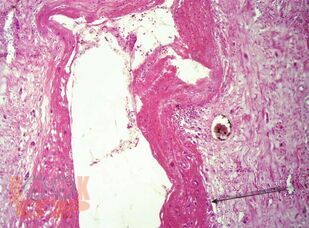

В монографии изложены современные представления об этиологии, патогенезе заболеваний беременности, родов и послеродового периода, патоморфологических изменениях в органах и тканях при акушерских заболеваниях и экстрагенитальных нозологиях, являющихся ведущими в структуре материнской смертности; представлены особенности патологоанатомического исследования и формулирования патологоанатомического диагноза при материнской смерти.